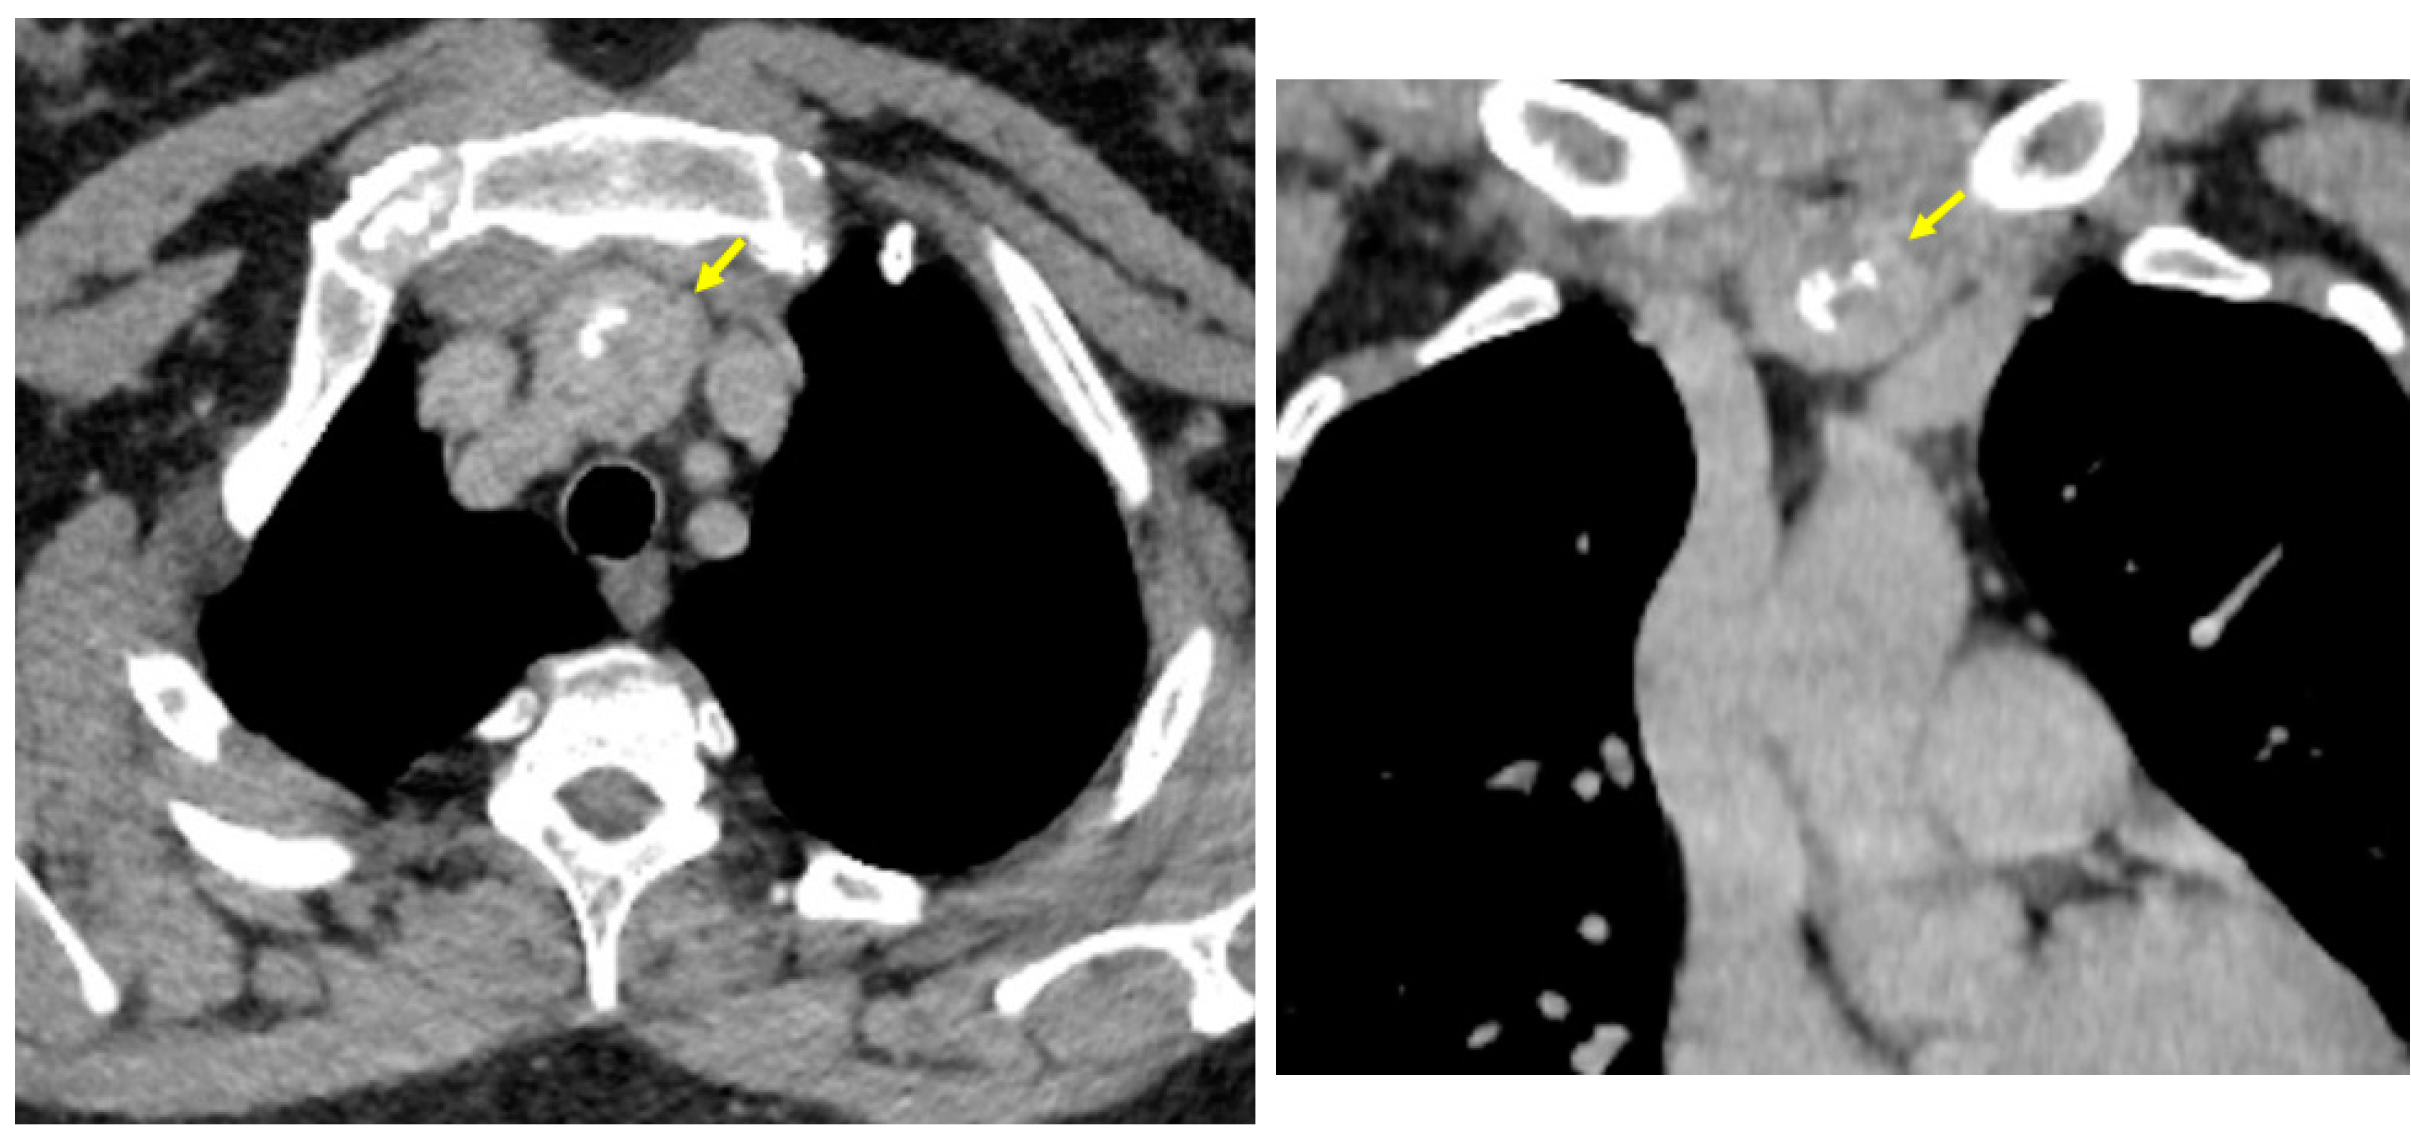

3.1.1. Baseline Admission: Identification of a Mediastinal Mass and an Adrenal Tumour Following Prior COVID-19 Infection

3.1.2. Endocrine and Imaging Investigations After One Year of Surveillance

- At the initial computed tomography, a small line of tissue was suspected to be the connective tissue between the orthotopic and ectopic thyroid, but it was not intra-operatory confirmed or after the post-surgery histological exam. This connective tissue facilitates the distinction between ectopic mediastinal tissue and a retrosternal extension of a cervical goitre [79];